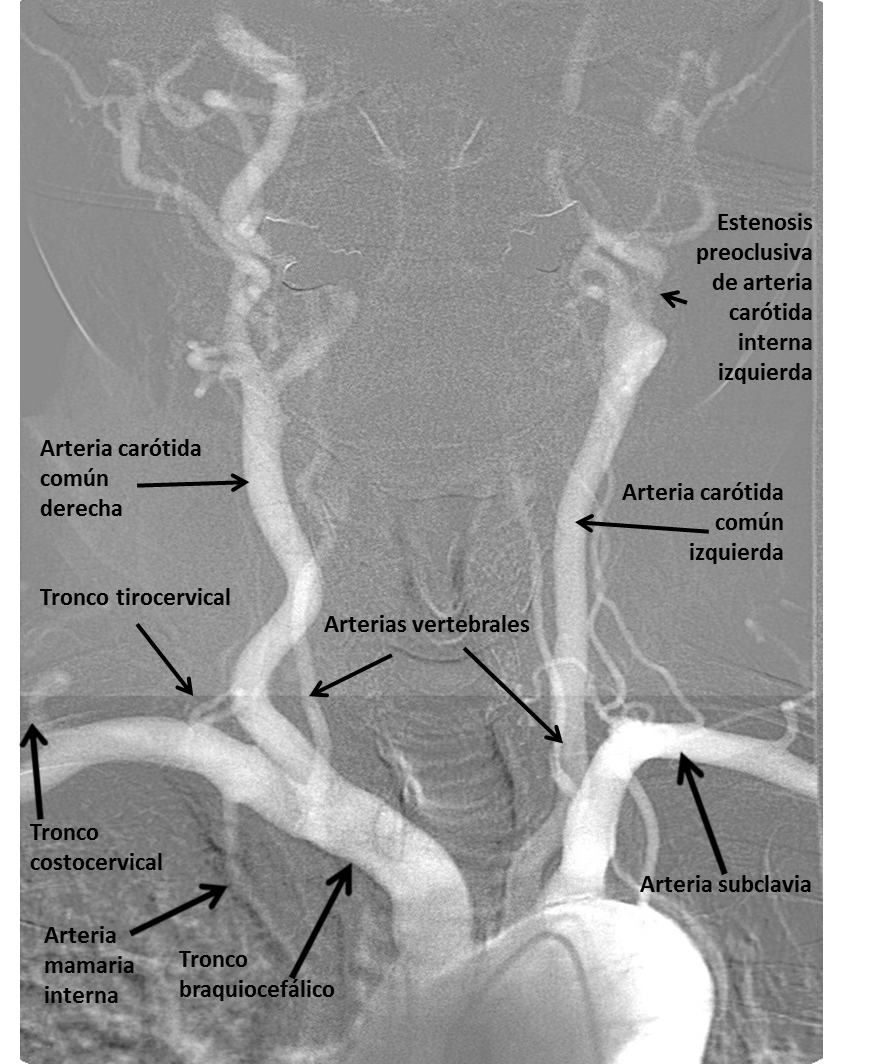

En esta entrada os presento las imágenes de arteriografía de una estenosis carotídea preoclusiva.

En la Imagen 1. podemos observar el arco aórtico y sus ramas principales (en orden): tronco braquiocefálico del que salen la arteria carótida común derecha y la arteria subclavia. La arteria carótida común se divide posteriormente en externa e interna. De la arteria subclavia sale la arteria vertebral, el tronco tirocervical, la arteria mamaria interna y el tronco costocervical. Posteriormente sale la arteria común izquieda y la arteria subclavia izquierda. En la arteria carótida común izquierda se observa un paso filiforme de contraste correspondiente a una estenosis carotídea.